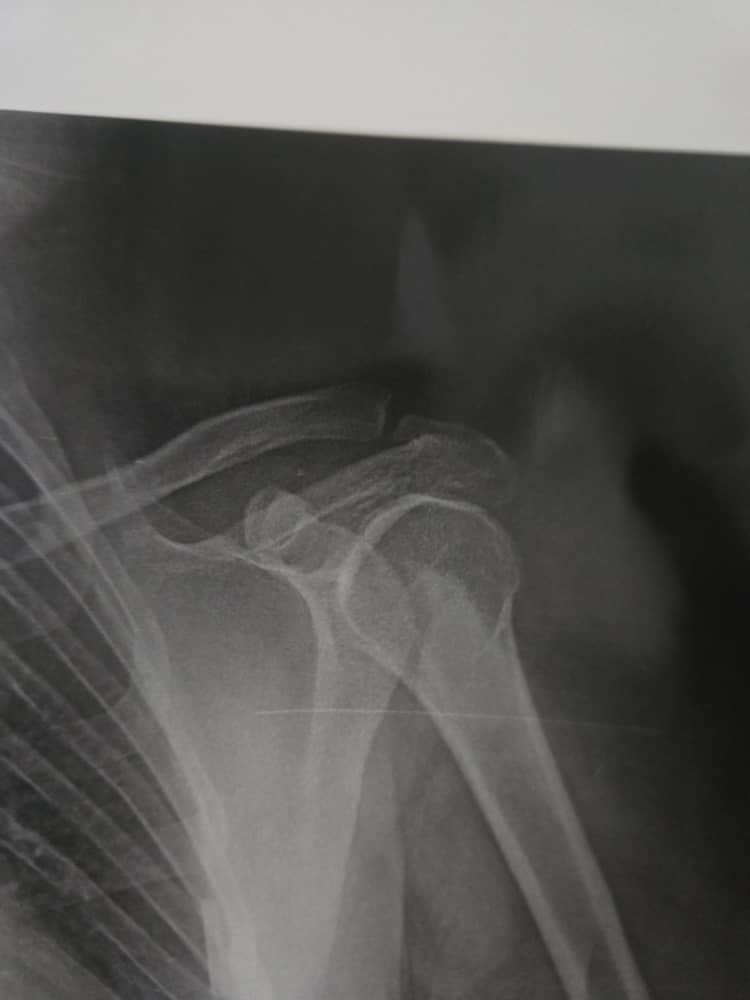

تقييم صورة شعاعية للكتف

هل الكتف طبيعي أم أن هناك أي علامات مرضية وإذا كان هناك ما التدبير المقترح

هذا لا يكفي للتشخيص او للنصح والارشاد عليك مراجعة طبيب روماتيزم او طبيب جراحة عظام للفحص السريري لاجراء اللازم